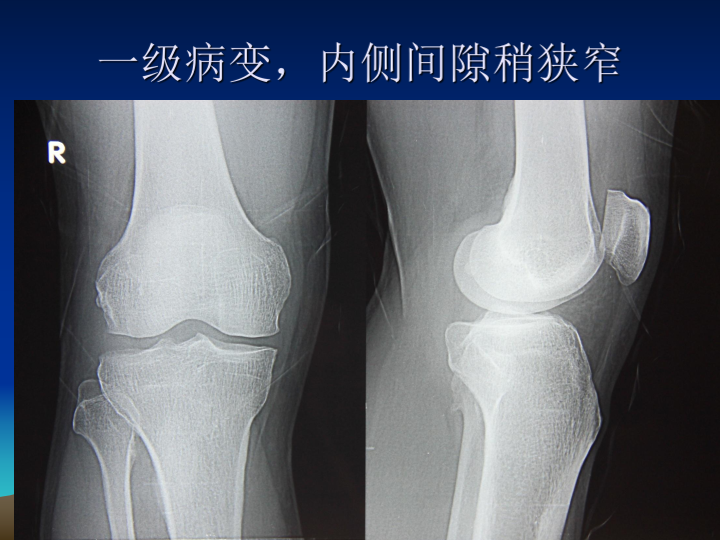

膝关节骨性关节炎阶梯治疗